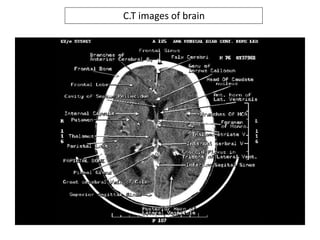

C.T images of brain